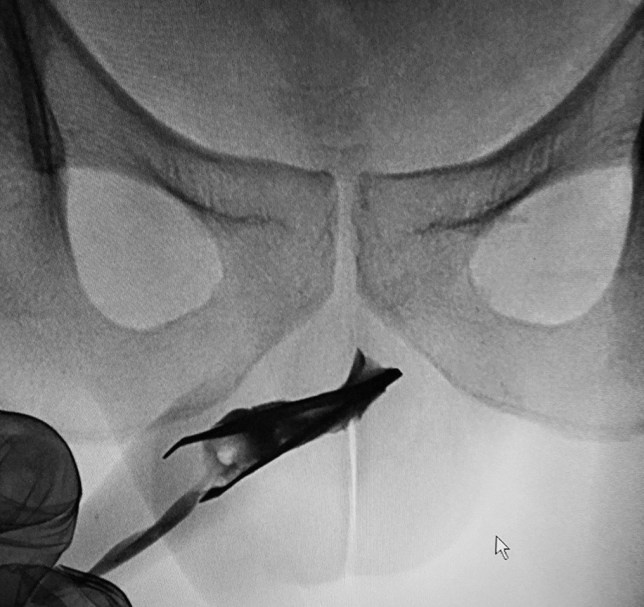

Доктора из Саудовской Аравии сообщают о пациенте, который четыре года ходил с пинцетом в уретре и лишь недавно попросил о помощи. Неназванный парень, которому сейчас 22 года, пришел в больницу, заявив, что инородное тело никак не мешало ему все эти годы, а теперь начало приносить легкий дискомфорт. Страдальца прооперировали и вынули пинцет под общим наркозом без особых проблем, после чего пациент попросту ушел из больницы.

Доктора пришли к выводу о том, что молодой человек не только экстремален в своем онанизме, но и, скорее всего, имеет кое-какие проблемы с головой. Ему настоятельно предложили психиатрическую помощь, но он сбежал. Надеемся, не для того, чтобы засунуть себе в уретру что-нибудь еще.